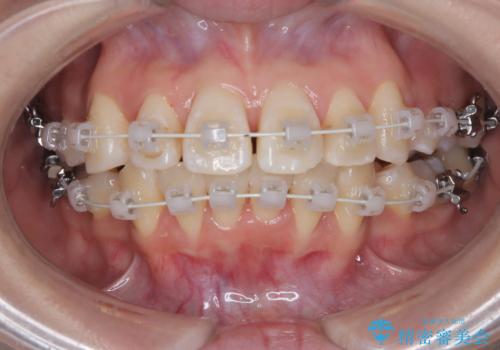

八重歯と正中のズレを解消!目立ちにくいワイヤー矯正で美しい歯並びへ

- 八重歯(叢生)と、上下の歯の中心線(正中)がずれていることを主訴にご来院されました。精密な検査の結果、歯列全体のスペースが大幅に不足しており、八重歯を正しい位置に配列し、正中のズレを改善するためには、上下左右の第一小臼歯を抜歯する必要があると診断。装置には、目立ちにくい審美ワイヤーを使用し、見た目を気にせず、機能性と審美性が完璧に整った咬み合わせを目指す治療計画を立案しました。

今回の矯正治療では、まず計画通り上下左右の小臼歯4本を抜歯し、八重歯や正中のズレを解消するための十分なスペースを確保しました。装置には、目立ちにくい白いブラケットとワイヤーを使用した審美ワイヤー矯正を採用。

八重歯: 突出していた八重歯を歯列内に誘導し、デコボコを解消しました。

正中のズレ: 歯を左右対称に移動させることで、上下の歯の中心線を正確に合わせ、顔全体のバランスも改善しました。

治療の結果、長年気にされていた八重歯と正中のズレが解消し、機能的にも整った理想的な歯並びを獲得。目立たない装置で治療を完遂し、自信を持って笑える美しい笑顔を手に入れていただけました。